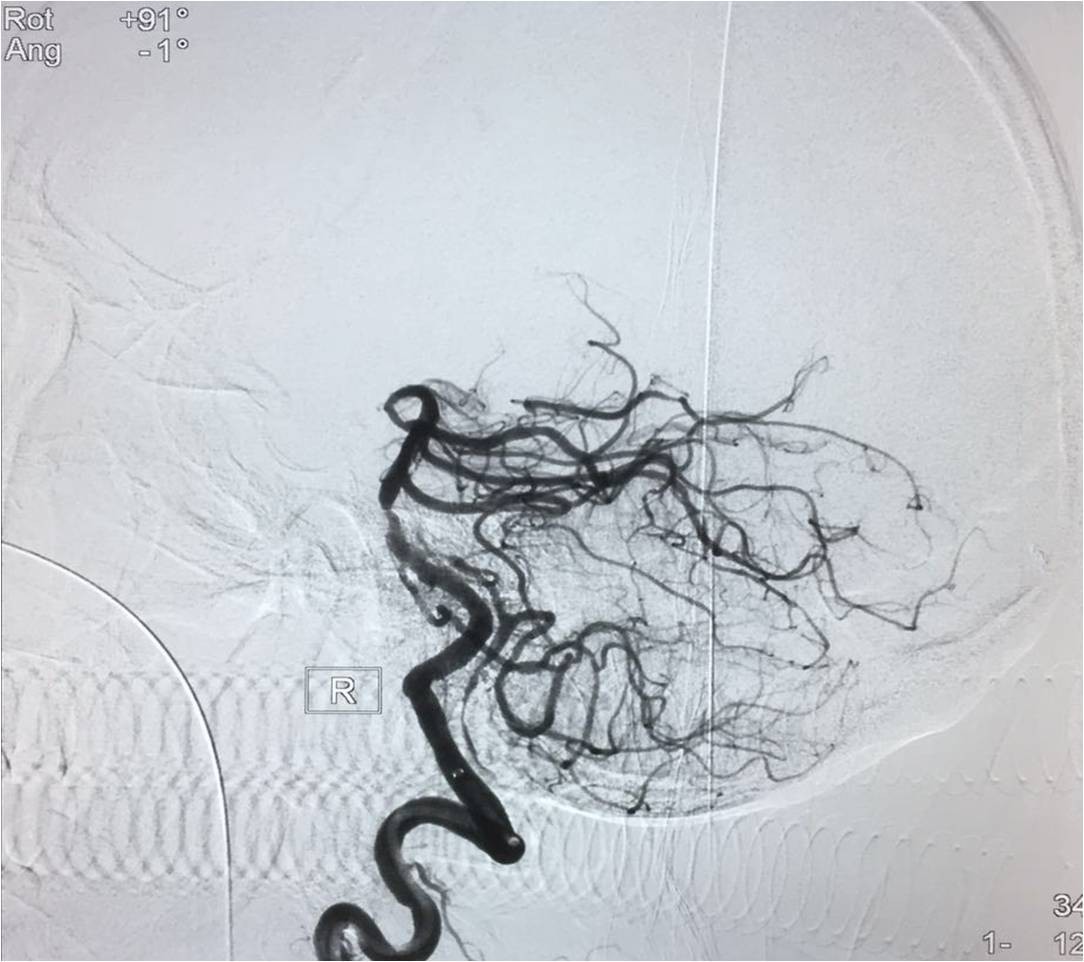

▼微导管定位

▼将Solitaire FR 送进微导管后将支架至于闭塞。部位远端,定位释放支架,保持原位5-10分钟后,将支架和微导管同时回撤。